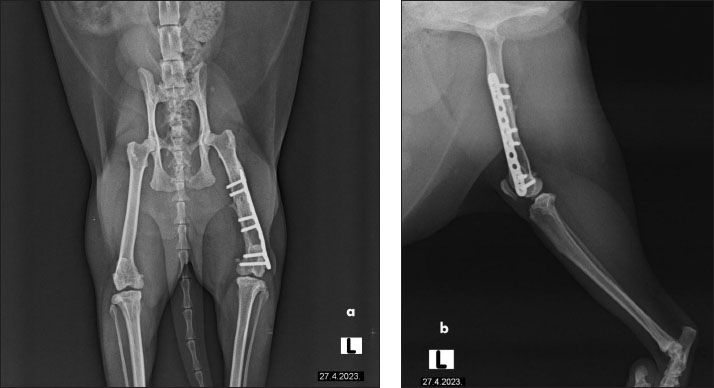

The owner reported continuous improvement, noting that the cat is increasingly bearing weight on the left hind limb, showing fewer signs of pain, and displaying an improved disposition. Follow-up radiographs revealed improvement in the condition of the femur post-therapy (Fig. 4). There is a noticeable improvement in bone structure, indicating enhanced healing and remodeling processes. After 2 months of intensive therapy and visible clinical improvement, the intervals between treatments were further extended. The radiograph shows the bone structure to be more consolidated, indicating effective recovery and remodeling (Fig. 5). Overall, the imaging suggests a positive outcome following treatment. In agreement with the owner, the treatments have continued on a monthly basis, and the cat continues to show progress.

Fig. 4. The radiographs of a cat’s left femur show (a) a ventrodorsal and (b) a mediolateral view demonstrating the femur after 1 month of LT, demonstrating reduced medullary transparency and early signs of bone consolidation.